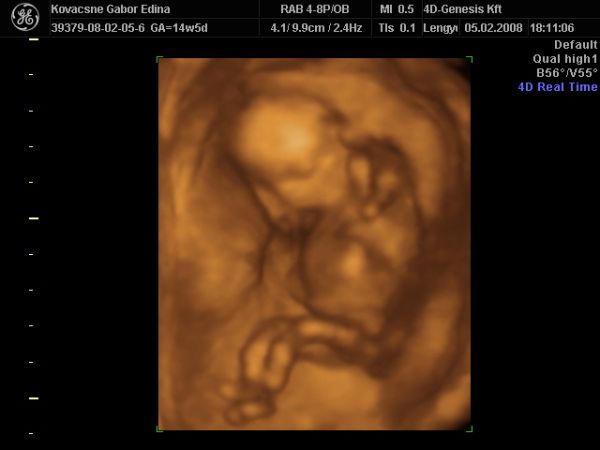

KISFIÚ 100%!!!

Annyira jó volt lányok a mozizás. Édesen kicsi a hely, de szépen berendezett, kellemes környezet. A hölgy, aki csinálta az UH-t nagyon kedves (néha mondjuk már sok), de inkább ilyen legyen

Mondta, hogy imádja az ilyen pici terhességeket, amikor még egyben lehet az apróságokat látni.

Babussal minden rendben. Ficánkolt össze-vissza. Lába keresztben, karja a feje mögött, mint aki fekszik egy nyugágyban a tengerparton. Hatalmas pocija van...kis beles

Ismét egy héttel nagyobb volt, 15+5 naposnak mérték. Ilyenkor már CRL-t nem néznek. Viszont 125 g, a könyv szerint egy 15 hetes magzat kb. 50 g...nem tudom mitől lehet.

Végig ébren volt, szopta a végén az ujját is. Imádom!

Ja, a kis kukiját pedig többször is megmutatta az én drágám, nem titkolózott hála istennek.